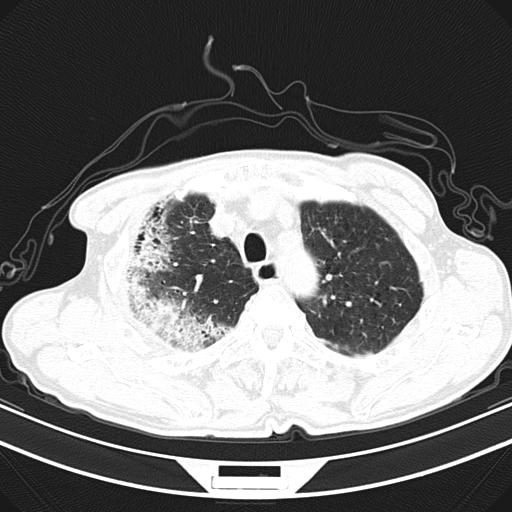

标题: CT23873:男,70,发烧咳嗽咳痰10余天,查痰结核菌阴性 [打印本页]

男,70,发烧咳嗽咳痰10余天,查痰结核菌阴性。否认以前有肺病史。治疗10天后症状减轻。 img]/upload/forum/2009/12/302117469692.jpg[/img]

影像所见:右上肺见一巨大厚壁空洞,内壁欠光整,右上肺广泛斑片状、大片状模糊阴影。

抗炎治疗10天后复查:右上肺模糊阴影明显减少。

诊断意见:考虑右上肺巨大含气囊肿并感染,建议继续治疗后复查。

不支持点:空腔壁较厚,欠光滑。询问病人是否有反复感染病史?

结核临床及影像,结核暂不考虑。

影像所见:右上肺见一巨大厚壁空洞,并见分隔,内壁欠光整,右上肺广泛斑片状、大片状磨玻璃阴影。

这例首先确定为感染性病变应该没问题,关键是怎么解释哪个大洞的问题。结核没有卫星病灶;脓肿没有液平;病毒感染?;真菌?;寄生虫?-----?